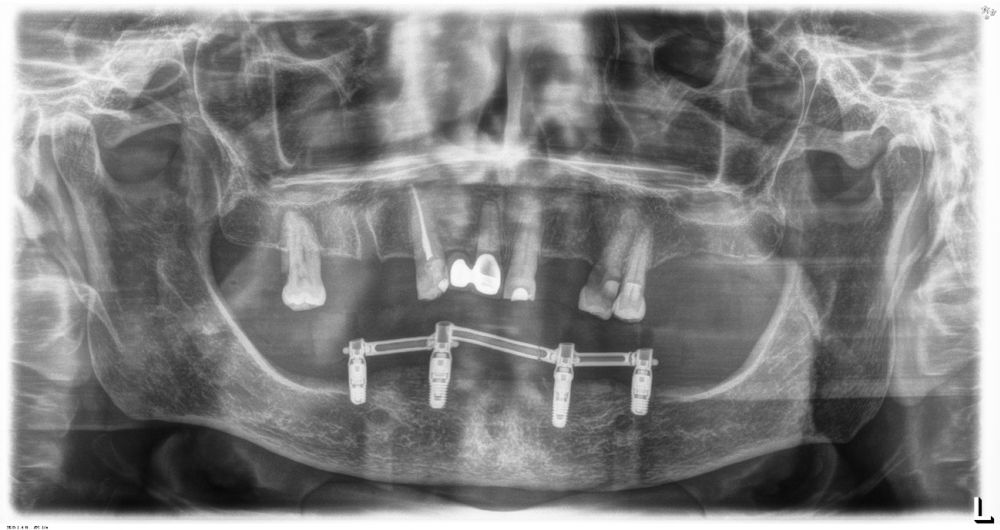

El análisis global de los 99 implantes reveló una pérdida ósea marginal media de 0,77 ± 0,26 mm en la superficie mesial y 0,79 ± 0,29 mm en la distal, valores que se mantuvieron dentro de los rangos considerados clínicamente aceptables para rehabilitaciones mandibulares. Cuando los implantes se categorizaron según su longitud, se observaron diferencias claras entre ambos grupos. Los implantes cortos (<10 mm) mostraron una pérdida ósea mesial media de 0,61 ± 0,23 mm y distal de 0,56 ± 0,22 mm, mientras que los implantes largos (≥10 mm) presentaron pérdidas significativamente mayores (mesial: 0,92 ± 0,19 mm; distal: 0,99 ± 0,17 mm). Dado que las pruebas de normalidad (Shapiro–Wilk) mostraron una distribución no normal en todos los grupos (p < 0,001), se aplicó la prueba no paramétrica de Mann–Whitney U. Los resultados confirmaron diferencias estadísticamente significativas tanto en la pérdida ósea mesial (U = 2068,5; p < 0,001) como en la distal (U = 2247,0; p < 0,005), indicando que los implantes cortos presentaron un comportamiento óseo más favorable que los implantes largos a lo largo del tiempo. Durante el tiempo de seguimiento que fue de media de 12,2 años (+/- 4,4; rango 6-23 años) no se objetivaron fracasos en ninguno de los implantes por lo que la supervivencia acumulada fue del 100%. El análisis del periodo de seguimiento mostró diferencias claras entre ambos grupos. Los implantes largos (≥10 mm) presentaron un tiempo medio de función de 14,1 ± 4,2 años (rango: 9–23 años), mientras que los implantes cortos (<10 mm) registraron un seguimiento significativamente menor, con una media de 9,8 ± 2,7 años (rango: 6–15 años). En las Figuras 3- 10 se muestran dos casos incluidos en el estudio, uno de cada situación descrita.